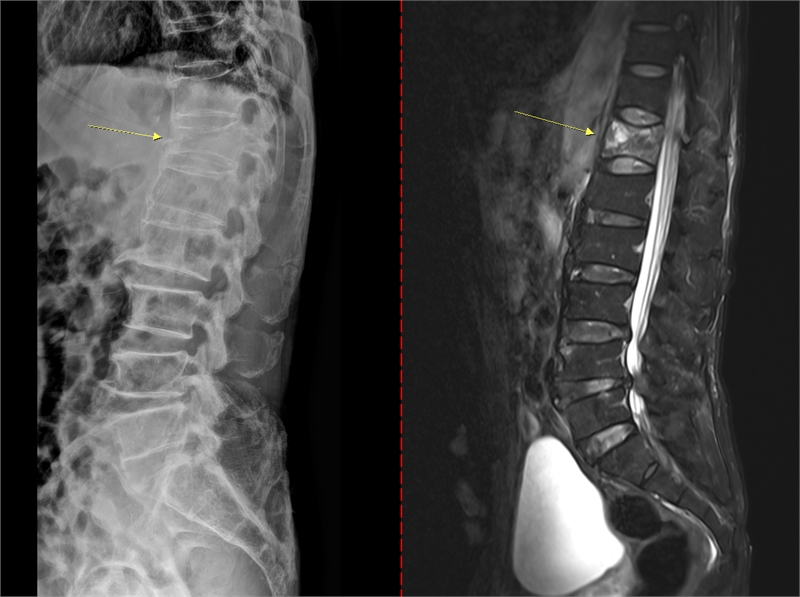

골다공증은 초기 징후가 뚜렷하지 않아 특히 주의해야 한다. 통증이나 자각 증상이 거의 없다가 시간이 지나 가벼운 충격만으로도 손목이나 대퇴골(엉덩이뼈)이 골절되면서 뒤늦게 진단되는 경우도 있다. 때로는 등이 굽거나 키가 줄어드는 척추 압박골절이 나타날 수도 있다. 치료 없이 방치하면 뼈는 점점 약해지고 척추와 손목, 대퇴골 골절 등 중대한 골절이 발생할 수 있다. 특히 대퇴골 골절은 고령 환자에서 수술 후 합병증, 장기 입원, 사망률 증가와 직결되는 중증질환이다. 척추 압박골절의 경우 자세 변화, 만성 통증, 보행 장애를 유발해 ▲활동량 감소 ▲근력 저하 ▲추가 골절의 악순환으로 이어진다.